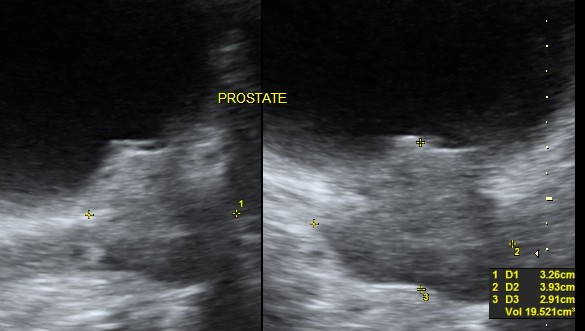

the median lobe prominence is well appreciated in the 2 d image also.

the next is a 3 d reconstruction , which shows the prominent median lobe prominence adjacent to the mass.